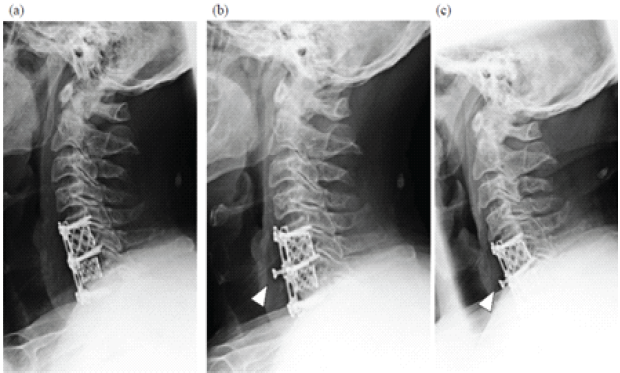

A 62-year-old male presented with gait disturbance, numbness, and muscle weakness due to cervical spondylotic myelopathy. He underwent C5–C7 ADF with a plate and cage at another hospital. Six months postoperatively, radiographs showed screw loosening and migration (Fig. 1).

Figure 1: Plain radiographs after anterior cervical decompression and fusion. Radiographs obtained in 1 week (a), 6 months (b), and 3.5 years (c) post-operatively are shown. Migration of the C6 screw is evident at 6 months (arrowhead), although no further progression was observed.